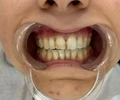

د. عائشة ألينيا يلماز

ألم تحت الأسنان السفلية

د. عائشة أليناء يلماز طبيبة أسنان

الصور